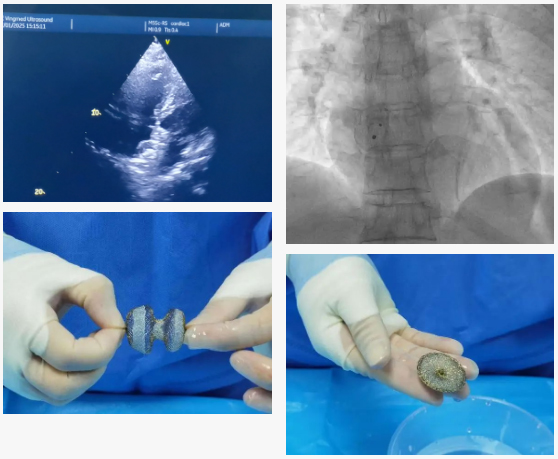

新技術(shù)上線!玉溪市中醫(yī)醫(yī)院成功開展首例先天性心臟病房間隔缺損介入微創(chuàng)封堵術(shù)

近日,在昆明市中醫(yī)醫(yī)院呂云主任的指導(dǎo)下,玉溪市中醫(yī)醫(yī)院介入手術(shù)團(tuán)隊(duì)聯(lián)合超聲影像科,成功完成本院首例經(jīng)皮房間隔缺損封堵術(shù)。

在呂云主任的指導(dǎo)下,術(shù)前仔細(xì)分析房間隔缺損的大小及毗鄰關(guān)系,充分預(yù)判了手術(shù)難度及術(shù)中可能遇到的情況。術(shù)中在多學(xué)科團(tuán)隊(duì)的協(xié)作下,順利送入ASD封堵器,于預(yù)期位置完成了封堵器的精準(zhǔn)釋放。

超聲及DSA透視下確認(rèn)封堵器形態(tài)良好,無殘余分流,各瓣膜活動(dòng)無異常,牽拉試驗(yàn)確定封堵器固定良好,遂完全釋放封堵器?;颊咝g(shù)后恢復(fù)良好,目前出院。

封堵器展示